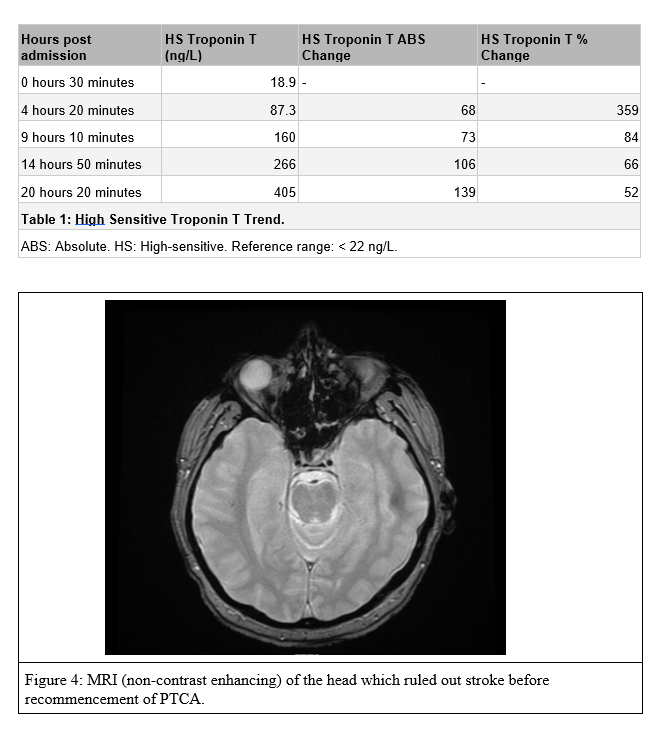

His lipid panel was abnormal, and the High-Sensitive Troponin T trended up—table 1.

In this case, with the emergence of the symptom of vision loss, PTCA was halted to allow the operator to rule out an acute cerebrovascular accident (CVA) through urgent CT head and MRI brain scans.